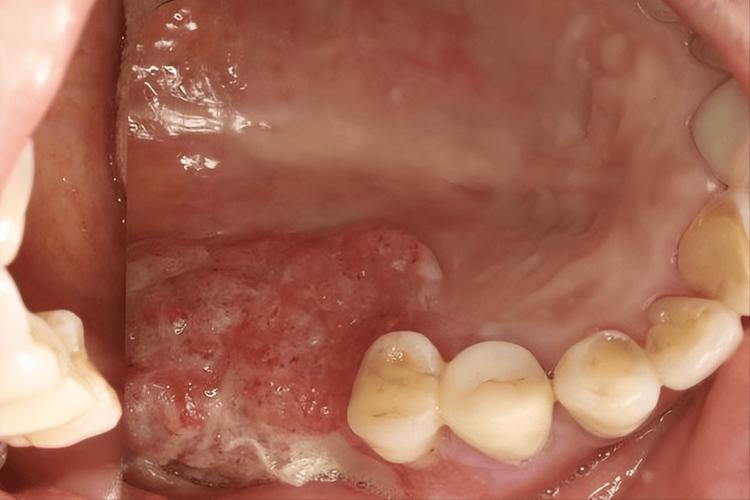

血疱 (Hemorrhagic Blister)

- 外观:这是最常见的一种,通常是突然出现的,边界清晰,半球形,里面充满了暗红色或紫红色的血液,摸起来软软的,不痛或只有轻微的胀痛感。

- 成因:最常见的原因是不小心咬到或食物(如硬壳坚果、薯片)划伤了口腔黏膜下的毛细血管,导致出血积聚在黏膜下,也可能与剧烈咳嗽、呕吐、用力擤鼻涕等有关。

- 特点:通常在1-2周内会慢慢吸收、颜色变浅,最后自行消退,期间泡液颜色可能会变成黄褐色或淡黄色,这是正常现象。